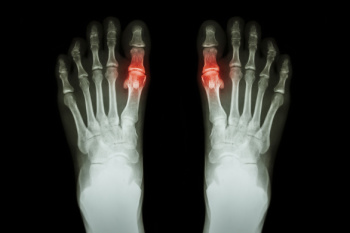

Workplace falls are a common cause of injury and can result from damaged ladders, slippery conditions, unmarked elevation changes, or leaning over guardrails. These accidents can lead to serious foot injuries such as sprains, fractures, or chronic pain that affect mobility and work performance. Prevention begins with choosing the right ladder for the job, using hazard warning signs, and keeping flooring clean and in good condition. A podiatrist can help treat foot injuries sustained from falls through diagnostic imaging, proper care, and targeted exercises to restore strength and stability. If you have experienced a fall affecting your lower extremities, or have lingering foot pain, it is suggested that you consult a podiatrist for a comprehensive evaluation and treatment to ensure a safe and healthy recovery.